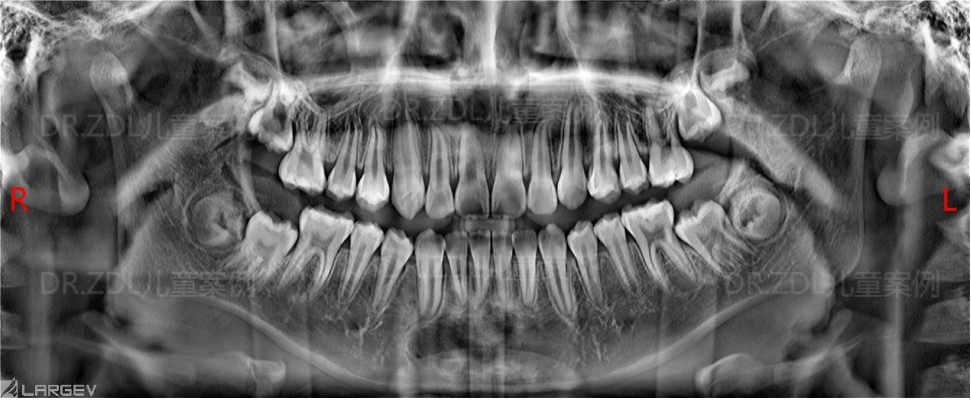

牙列:恒牙列,上前牙唇倾,上牙弓方圆形,l 度拥挤。下牙方圆形,l 度拥挤,上下牙弓匹配,17、27、37、47 未萌出。

双侧髁状突形态正常,两侧对称,18、28、38、48牙胚均可见,牙根牙槽骨正常。

骨性 II 类,均角,上前牙轻度唇倾,下前牙唇倾,上颌前突,下颌骨后缩。